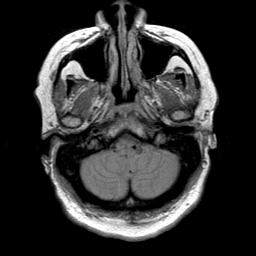

Cerebral hemorrhage, MR Study mr-pd -- Slice #4

[Home][Help][Clinical] Slice 4